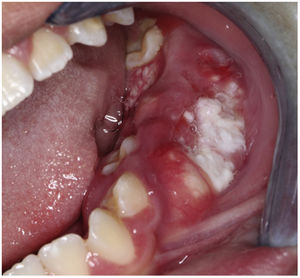

An 11-year-old boy was consulted because of local pain and paresthesia of the left lower lip during an unknown amount of time. He had a history of grade II ependymoma, which was appropriately treated with surgery and radiotherapy and controlled routinely. He had no systemic symptoms, known allergies or medical history of any other illness. Extra-oral examination revealed no anomalies. Intraorally, a mass involving both the buccal and lingual gingiva between the lower left second molar and lower left first premolar was observed. An extensive verrucous white patch was covering the buccal side of the mass, while cystic-like white nodules with superficial blood vessels were also present on both the lingual and buccal sides of the tumor (Fig. 1). The teeth involved in the mass were mobile. Cone-beam computed tomography revealed a well-defined large radiolucency involving the whole thickness of the posterior left mandible perforating the buccal bone plate (Fig. 2). An incisional biopsy was taken which showed a tumoral mass composed of multiple branching keratin-filled crypts sheets lined by epidermoid epithelial cells. The endophytic epithelial growth pattern burrowed deep inside into the alveolar bone, forming a complex network of connected canaliculi, resembling rabbit burrows. The epithelial cells were well differentiated, and no atypia, mitosis, perineural nor lymphovascular invasion was observed. A chronic inflammatory infiltrates consisting mainly of lymphocytes with local areas of neutrophil accumulation was observed in some areas of the stroma (Fig. 3). The lesion was diagnosed as a carcinoma cuniculatum of the oral cavity. Differential diagnosis with a solid variant of an odontogenic keratocyst was done due to its histopathological similarity. The CT scan examination revealed no lymph node involvement and no metastasis, and the patient was referred for surgical treatment. The patient was controlled with regularity and no recurrences have been observed after a 5-years-follow up period.